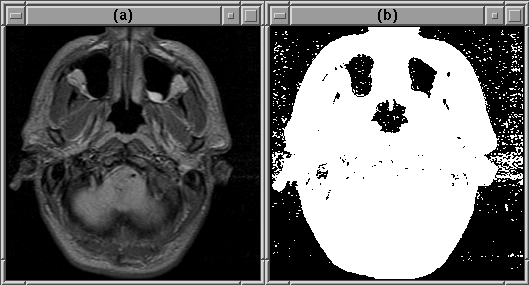

producing a binary image volume. The result of this threshold is shown

in Figure 7.4 for slice 1 of Data Set 1. Notice

that the binary image contains ``speckle'' outside the head region and

that there are misclassified regions within the head. This ``noise''

is removed using morphological operations.

Figure 7.4: An initial head mask produced using an

automatic threshold. (a) Original image. (b) Initial head mask.